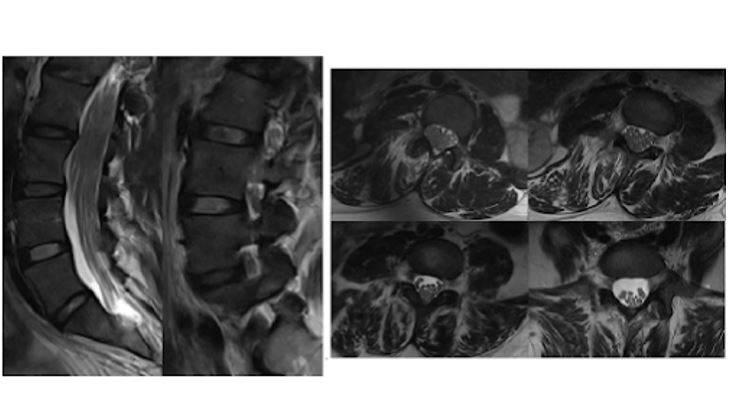

RM columna lumbosacra. Cortes sagitales y axiales en secuencias TSE potenciadas en T2. Engrosamiento simétrico de las raíces nerviosas de la cola de caballo en el canal lumbar y en los agujeros de conjunción que refleja una hipertrofia radicular difusa. Se observa también atrofia muscular grasa bilateral de la musculatura paravertebral posterior, de predominio derecho.

Enfermedad de Charcot-Marie-Tooth (CMT).